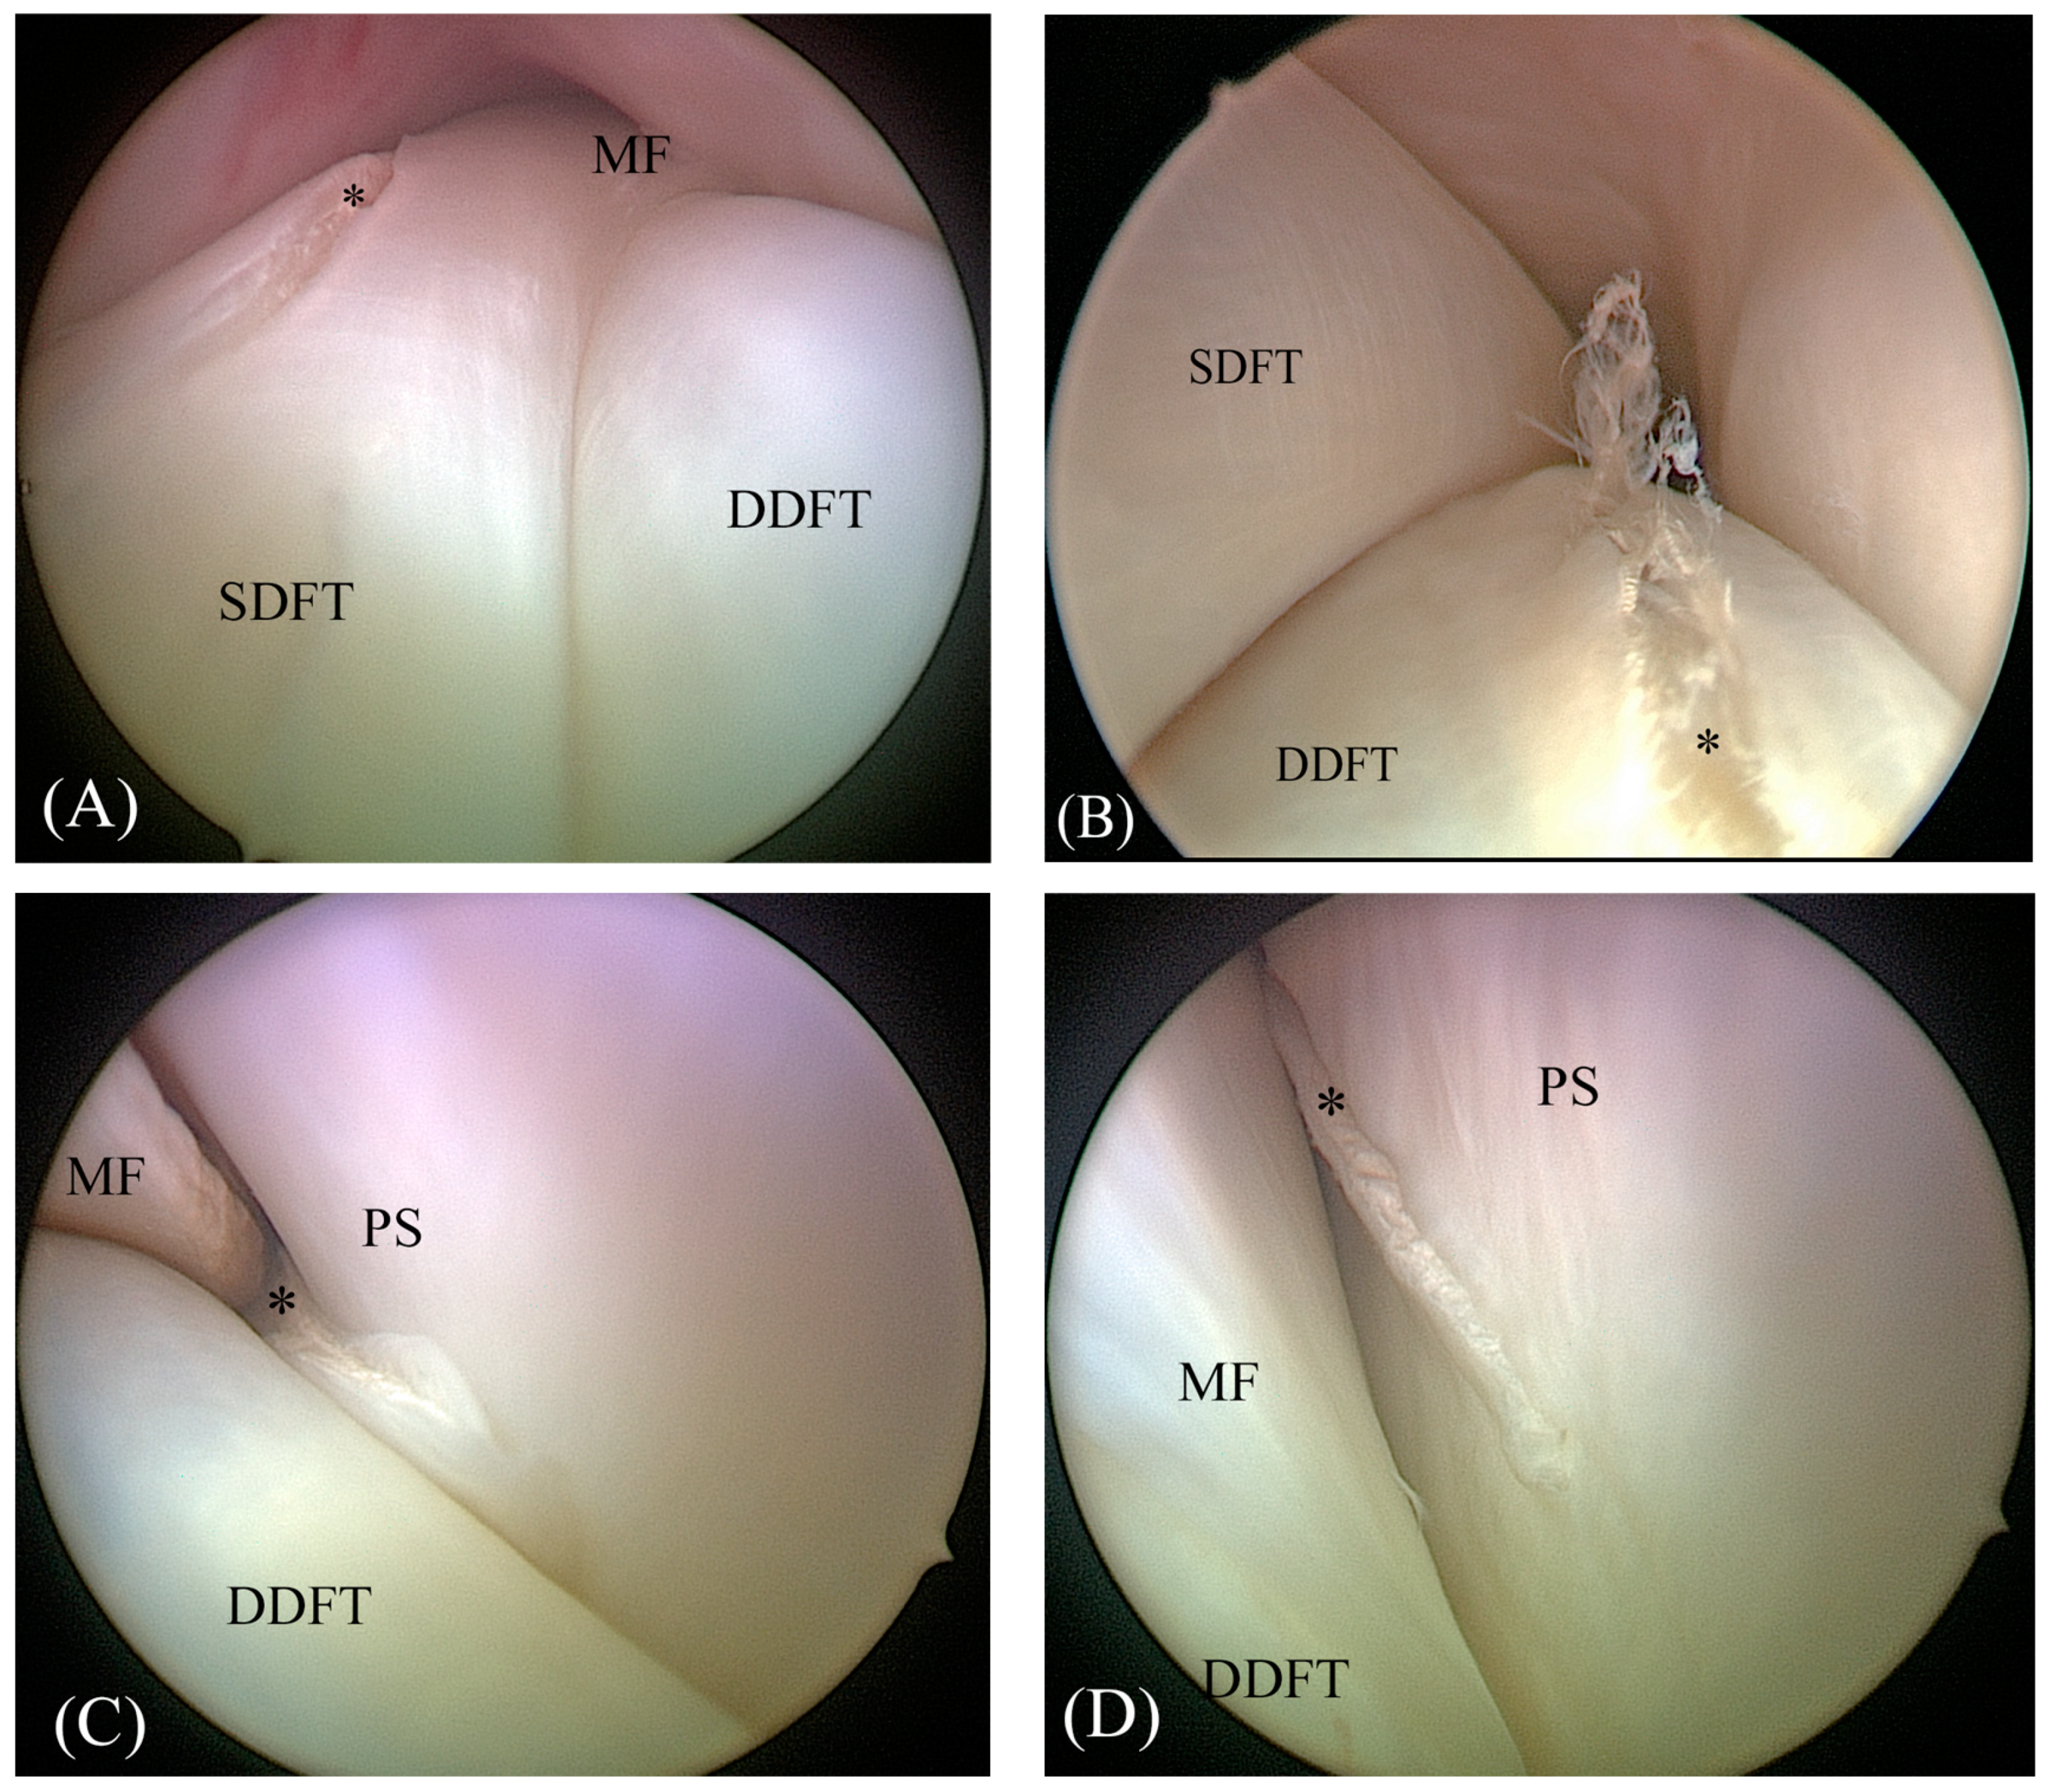

2.2. Tenoscopic Procedure